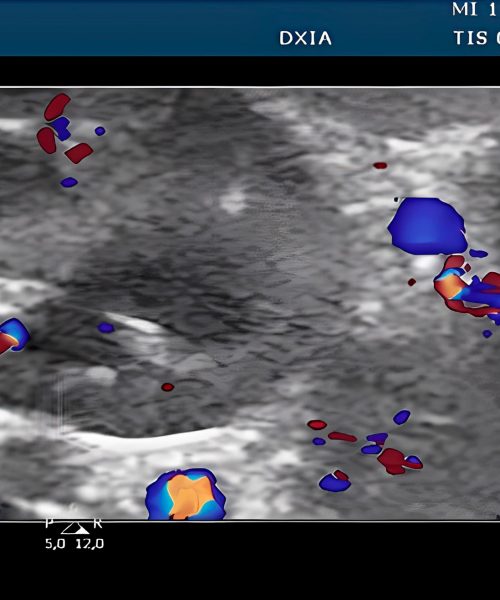

Ofrezco especialización en ecografía veterinaria y una colaboración integral basada en vuestro historial clínico.

Valido la precisión diagnóstica comparando las imágenes ecográficas con los hallazgos quirúrgicos reales.

Garantizo transparencia y confianza exhibiendo en este apartado casos reales con su correlación intraoperatoria documentada.